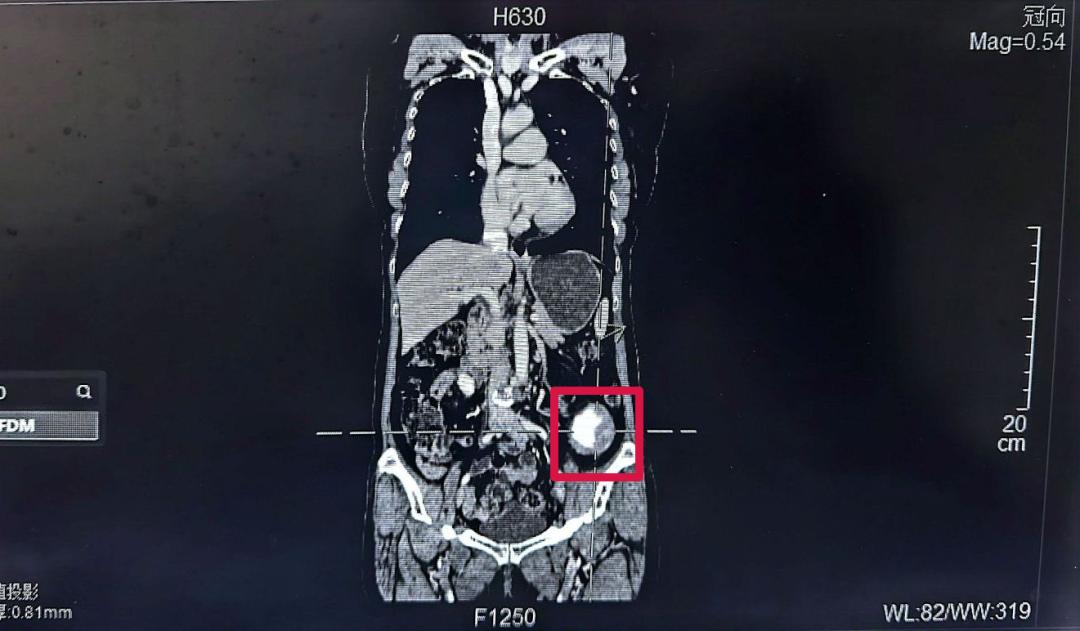

69歲的黃女士(化名)最近有些不安,她在自己左下腹部無意間摸到了一個腫塊,足有蘋果大??!焦急之下,她前往醫(yī)院進行CT檢查,但結果卻讓她的心懸了起來,在她的左下腹腔發(fā)現(xiàn)一個巨大占位,里面還有鈣化(骨頭樣結構)。面對這個陌生的診斷,黃女士和家人一時手足無措,對治療方案充滿疑慮。

幾經(jīng)了解問詢,黃女士找到了泉州一院胃腸外科的林鴻悅主任團隊。林主任仔細詢問了病史,為她做了詳細檢查,并認真研判了CT影像,初步判斷,這極可能是一個長在腹腔深處(腹膜后)的腫瘤,位置刁鉆,且情況復雜。

林鴻悅主任團隊迅速組織了術前討論。深入分析病情后,團隊意識到這次手術極具挑戰(zhàn)性,這個腫瘤長在“腹膜后”。這個位置就像腹腔的“后倉庫”,空間狹窄,里面“住”著人體最重要的大血管(如腹主動脈、下腔靜脈)、神經(jīng)叢和器官(如腎臟、胰腺、腸道)。手術稍有不慎,就可能引發(fā)難以控制的大出血或損傷關鍵臟器,后果不堪設想。

同時這個腫瘤性質罕見且兇險,初步影像提示腫瘤伴有鈣化(骨頭樣結構),團隊高度懷疑這是一種極其罕見的惡性腫瘤--去分化脂肪肉瘤伴骨肉瘤分化。這種腫瘤不僅惡性程度高、侵襲性強,而且其中的“骨肉瘤分化”成分,意味著腫瘤內部可能像骨頭一樣堅硬,大大增加了完整剝離的難度。